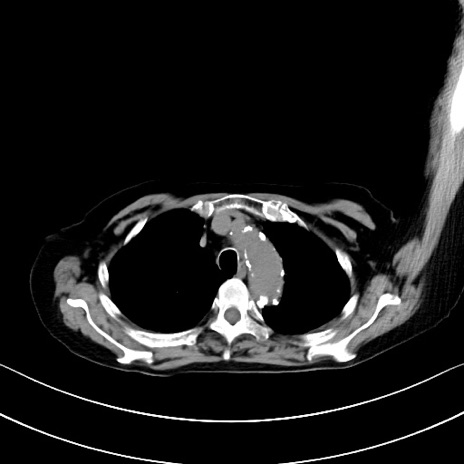

横断像

他院CT